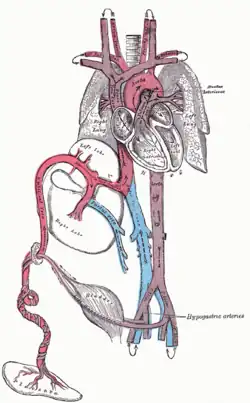

Sistema circulatório

Antes do nascimento

O coração e os vasos sanguíneos do sistema circulatório formam-se relativamente cedo durante o desenvolvimento embrionário, mas continuam a crescer e a desenvolver-se em complexidade no feto em crescimento. Um sistema circulatório funcional é uma necessidade biológica, uma vez que os tecidos dos mamíferos não conseguem crescer mais do que algumas camadas de células sem um fornecimento sanguíneo ativo. A circulação sanguínea pré-natal é diferente da circulação pós-natal, principalmente porque os pulmões não estão a ser utilizados. O feto obtém oxigénio e nutrientes da mãe através da placenta e do cordão umbilical.[24]

O sangue da placenta é transportado para o feto pela veia umbilical. Cerca de metade deste entra no ducto venoso fetal e é levado para a veia cava inferior, enquanto a outra metade entra no fígado propriamente dito a partir do rebordo inferior do fígado. O ramo da veia umbilical que irriga o lobo direito do fígado junta-se primeiro à veia porta. O sangue desloca-se então para o átrio direito do coração. No feto, existe uma abertura entre o átrio direito e o esquerdo (o forame oval), e a maior parte do sangue flui do átrio direito para o esquerdo, desviando-se assim da circulação pulmonar. A maior parte do fluxo sanguíneo é para o ventrículo esquerdo, de onde é bombeado através da aorta para o corpo. Parte do sangue desloca-se da aorta através das artérias ilíacas internas para as artérias umbilicais e entra novamente na placenta, onde o dióxido de carbono e outros resíduos do feto são absorvidos e entram na circulação da mãe.[24]

Parte do sangue do átrio direito não entra no átrio esquerdo, mas entra no ventrículo direito e é bombeado para a artéria pulmonar. No feto, existe uma ligação especial entre a artéria pulmonar e a aorta, denominada ‘’ducto arterioso’’, que encaminha a maior parte deste sangue para longe dos pulmões (que não estão a ser utilizados para a respiração neste momento, uma vez que o feto está suspenso no líquido amniótico).[24]

Desenvolvimento Pós-Natal

Após o nascimento, com a primeira respiração, o sistema altera-se repentinamente. A resistência pulmonar é drasticamente reduzida, forçando mais sangue a entrar nas artérias pulmonares a partir do átrio e ventrículo direitos, em vez de fluir através do forame oval para o átrio esquerdo. O sangue dos pulmões viaja através das veias pulmonares até ao átrio esquerdo, produzindo um aumento de pressão que fecha o foramen oval, completando a separação do sistema circulatório. Posteriormente, o forame oval é designado por fossa oval. O ductus arteriosus fecha-se normalmente no espaço de um a dois dias após o nascimento, deixando o ligamento arterioso, enquanto a veia umbilical e o ducto venoso fecham-se geralmente dois a cinco dias após o nascimento, deixando o ligamento redondo e o ligamento venoso, respetivamente.